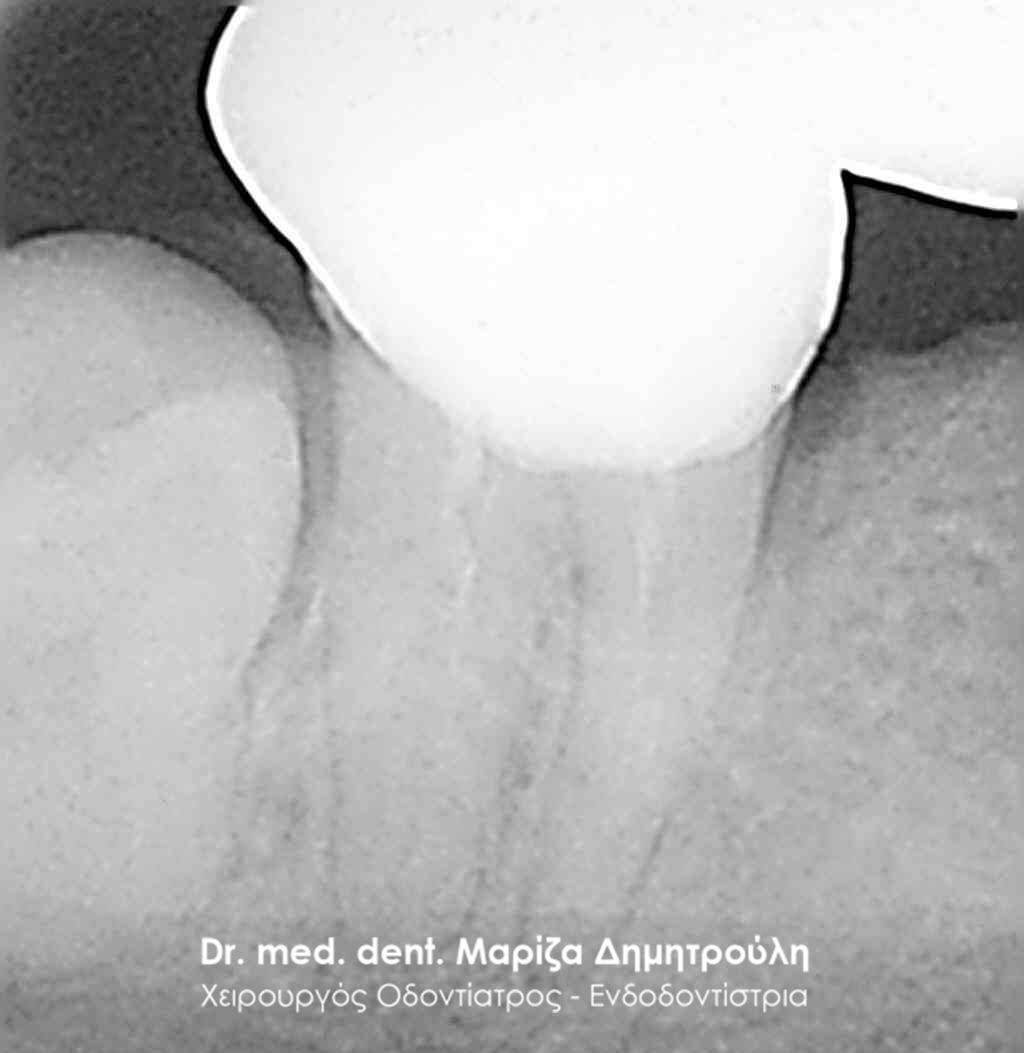

Η ασθενής περιγράφει έναν έντονο συνεχόμενο πόνο στη δεξιά πλευρά της άνω γνάθου που δεν την αφήνει τις τελευταίες μέρες μα εργαστεί. Μετά την κλινική και ακτινογραφική εξέταση της περιοχής διαπιστώθηκε οτι το υπαίτιο δόντι για την πρόκληση των έντονων συμπτωμάτων ήταν ο δεύτερος δεξιός άνω γομφίος, ο οποίος διέθετε ένα παλιό βαθύ σφράγισμα που πίεζε το νεύρο του δοντιού.

Μετά τη χορήγηση τοπικής αναισθησίας αφαιρέθηκε το παλιό σφράγισμα και εντοπίστηκαν οι ριζικοί σωλήνες του δοντιού (βλέπε φωτογραφία). Μετά την κατάλληλη επεξεργασία των ριζικών σωλήνων και εφόσον το δόντι ήταν ασυμπτωματικό η απονεύρωση ολοκληρώθηκε με την έμφραξη των ριζικών σωλήνων με ειδικό εμφρακτικό υλικό.

ΠΡΙΝ